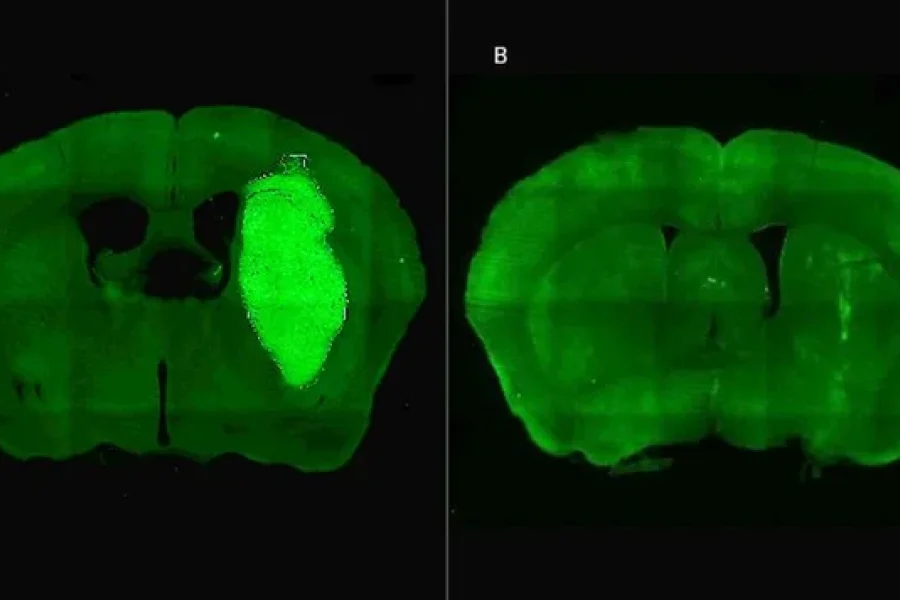

Especialistas del Consejo Nacional de Investigaciones Científicas y Técnicas (CONICET) identificaron una nueva estrategia terapéutica para frenar el desarrollo del glioblastoma, la cual en estudios in vitro y preclínicos logró volverlo más sensible a la quimioterapia y la radioterapia. El avance se describe en la revista Life sciences.

“Descubrimos que el bloqueo de una proteína llamada Foxp3, que se expresa en las células del glioblastoma, potencia la efectividad de la quimioterapia y la radioterapia. Los resultados del estudio son alentadores para quienes desde la ciencia buscamos aportar al desarrollo de opciones terapéuticas reales y efectivas para los pacientes con este tumor. La estrategia terapéutica se probó con éxito en estudios in vitro y preclínicos y sin duda nuestra esperanza es que se pueda probar en ensayos clínicos en el futuro, pero aún son necesarias investigaciones adicionales para llegar a eso”, afirma Marianela Candolfi, líder del trabajo e investigadora del CONICET en el Instituto de Investigaciones Biomédicas (INBIOMED, CONICET-UBA).

Candolfi y colegas utilizaron una terapia génica experimental basada en una molécula muy pequeña o péptido llamado P60, desarrollado por Juan José Lasarte en la Universidad de Navarra, en España, que atraviesa la membrana celular e inhibe la proteína Foxp3. “Cuando en experimentos de laboratorio bloqueamos Foxp3 utilizando P60, la respuesta de las células de glioblastoma a la radioterapia y a una variedad de drogas quimioterapéuticas mejoró notablemente”, destacó la investigadora del CONICET.

Además, P60 tuvo efectos antitumorales directos, reduciendo la viabilidad y la migración de las células de glioblastoma e inhibiendo la proliferación de células endoteliales que son clave para la progresión del tumor. Para evaluar estos efectos, los autores del estudio utilizaron una variedad de modelos celulares murinos (de roedor) y humanos. “En particular, los cultivos derivados de biopsias de pacientes con glioblastoma desarrollados por nuestro colaborador Guillermo Videla Richardson, del Instituto FLENI, son muy útiles para representar la heterogeneidad de estos tumores”, indicó Candolfi.